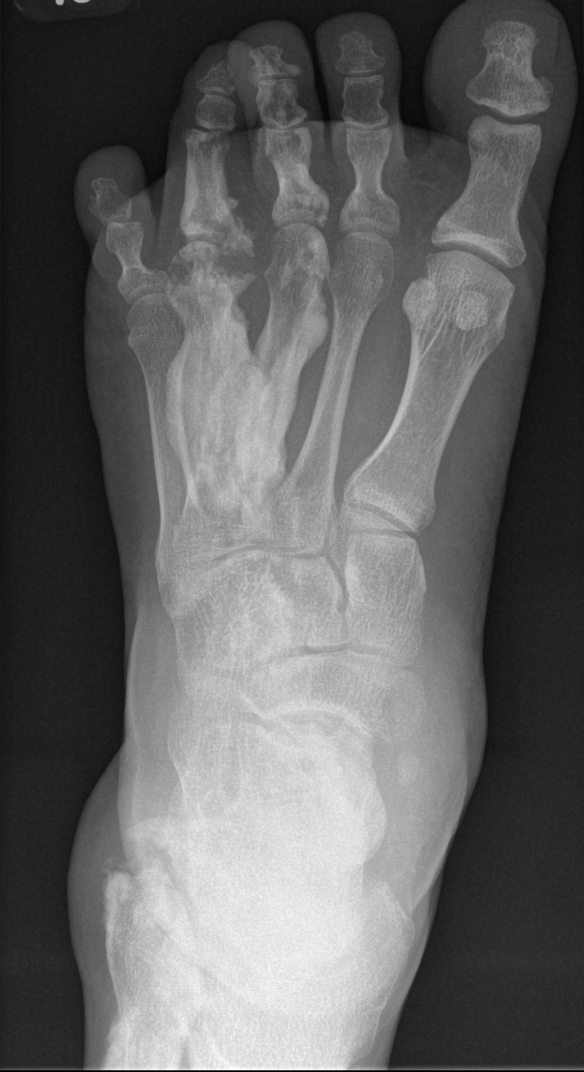

Usually affects lower limb

- lower limb (67%), upper limb (33%), spine (17%), head (8%)

X-ray

Sclerotic lesions of bones

- undulating cortical hyperostosis

- look like wax dripping down the side of a candle